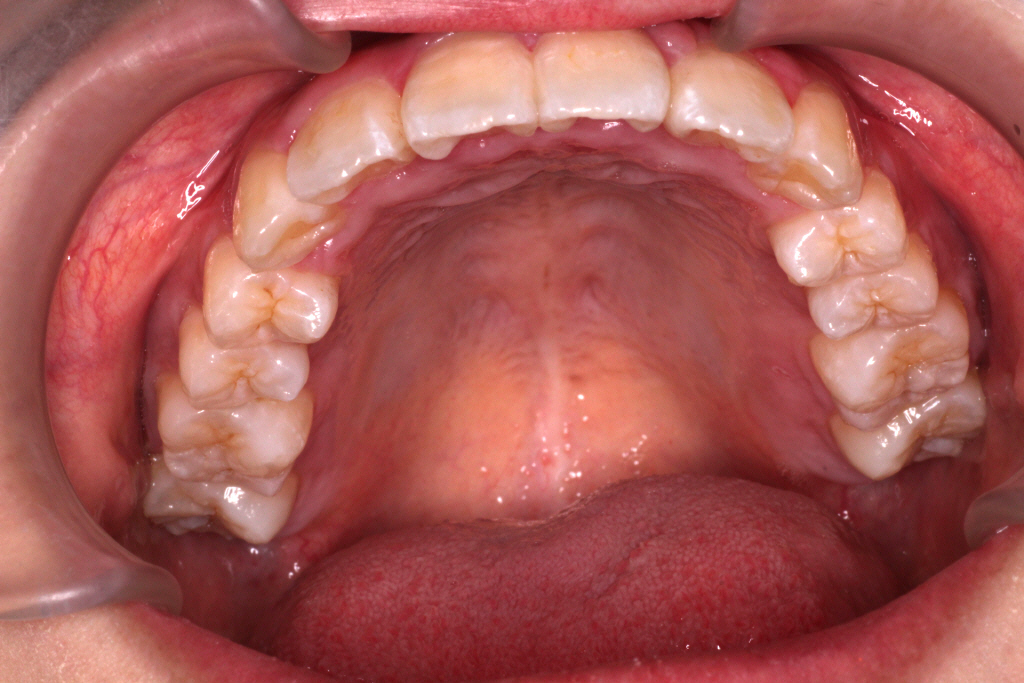

初診時のお口の中の状態です。

上の前から2番目の歯が下の歯列より内側にあり叢生です。

側方の上下の咬合関係が理想の上1本に対して下2本の理想的な噛み合わせではない。

歯列の幅がせまい。